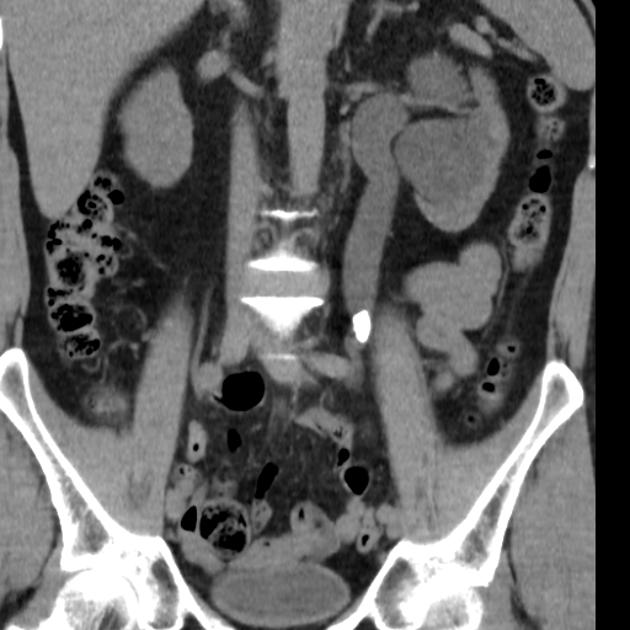

This case will challenge learners to think about sepsis diagnosis and management in the context of a patient with a significant cardiac history and a dangerous source of infection — the septic ureteric stone.

Denise is a 59-year-old female who presents with a 7-day history of urinary symptoms, fever, and left flank pain. She has a history of STEMI 5 years ago with chronic left-sided heart failure. She becomes unstable in the ER, requiring judicious fluid resuscitation, vasopressors, and empiric antibiotic treatment. The team leader needs to consider the history and arrange renal imaging to discover the severe sepsis is secondary to an infected ureteric calculus. From there, emergent urologic consultation and admission to hospital are warranted.